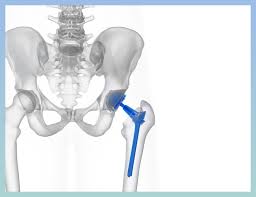

- 고관절 전치환술(Total Hip Arthroplasty, THA): 골관절염이나 류마티스 관절염, 골절 등에 널리 사용되는 방식으로, 관절 전체를 인공 관절로 교체합니다.